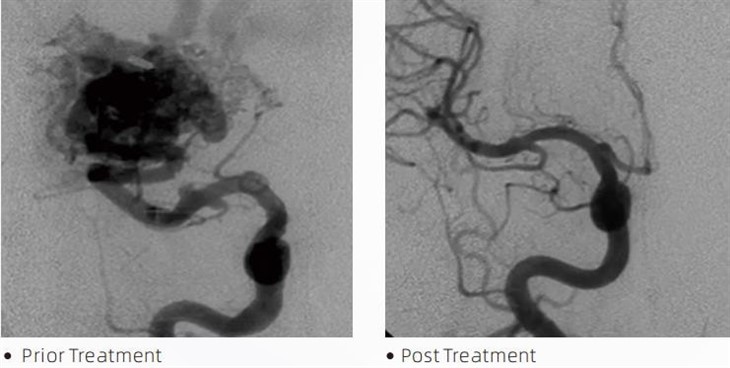

ลาวาที.เอ็มกาวอุดเส้นเลือดเป็นอุปกรณ์ทางการแพทย์ที่ใช้โดยนักรังสีวิทยาด้านรังสีรักษาในระหว่างขั้นตอนการบุกรุกน้อยที่สุดเพื่อรักษาสภาพต่างๆ เช่น หลอดเลือดสมองโป่งพอง หลอดเลือดแดงผิดรูป และเนื้องอก กาว Lava embolic มีประโยชน์มากมายสำหรับแพทย์และผู้ป่วย ทั้งในแง่ของความปลอดภัย ใช้งานง่าย และประสิทธิผล ลาวาสามารถปิดหลอดเลือดได้อย่างรวดเร็วและมีประสิทธิภาพ กระบวนการนี้เกี่ยวข้องกับการฉีดกาวโดยตรงเข้าไปในหลอดเลือดเป้าหมาย ซึ่งมันจะรวมตัวและแข็งตัวเป็นก้อนคล้ายหล่อที่เติมหลอดเลือดโป่งพองหรือรูปร่างผิดปกติ จากนั้นจะตัดการไหลเวียนของเลือดไปยังรอยโรคอย่างมีประสิทธิภาพ ป้องกันไม่ให้แผลแตกและลดความเสี่ยงของความเสียหายถาวรหรือโรคหลอดเลือดสมอง ลาวาประกอบด้วยลาวา-12 ลาวา-18 และลาวา-34 แต่ละสูตรได้รับการออกแบบมาเพื่อตอบสนองความต้องการทางคลินิกโดยเฉพาะ ลาวา-18 เป็นสูตรมาตรฐานสำหรับการใช้งานทั่วไป ลาวา-34 คือกาวที่มีความหนืดสูงสำหรับภาชนะที่มีการไหลสูง ในขณะที่ลาวา-12มีความหนืดต่ำกว่าและไหลได้มากกว่า ทำให้มีไมโครเวสเลสส่วนปลาย ด้วยตัวเลือกเหล่านี้ นักรังสีวิทยาแบบแทรกแซงสามารถเลือกสูตรลาวาที่เหมาะสมเพื่อให้ได้ผลลัพธ์ที่ดีที่สุด คุณสมบัติที่โดดเด่นที่สุดอย่างหนึ่งของ Lava คือคุณสมบัติที่ไม่เหนียวเหนอะหนะ สารนี้เป็นสูตรพิเศษเพื่อให้คงตัวจนกว่าจะถึงพื้นที่เป้าหมาย ลักษณะเฉพาะนี้หมายความว่ากาว Lava embolic สามารถวางได้อย่างแม่นยำภายในหลอดเลือดแดงและคงอยู่ที่นั่นโดยไม่เกาะติดหรือยึดเกาะกับเนื้อเยื่อรอบๆ